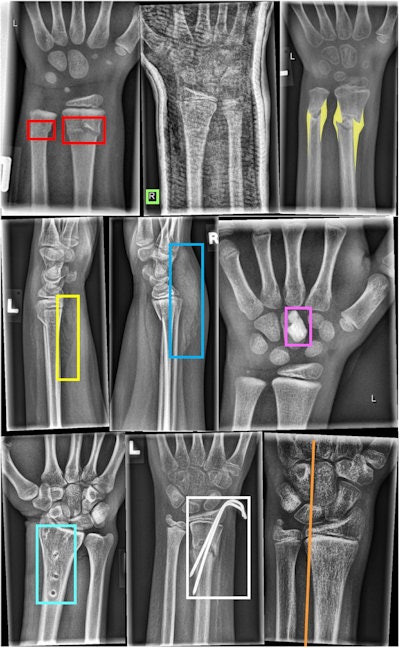

Examples of different objects labeled by human experts. In the first row, from left to right: Fracture (bounding box), text (bounding box), periosteal reaction (polygon). In the second row, from left to right: Pronator quadratus sign (bounding box), soft-tissue swelling (bounding box), foreign body (bounding box). In the last row, from left to right: Bone anomaly (bounding box), metal (bounding box), and axis (line). The middle radiograph in the first row shows a cast. The right images in the first and third row were tagged with osteopenia. Image courtesy of Scientific Data.Between March 2018 and February 2022, several pediatric radiologists with between six and 29 years in musculoskeletal radiology validated all annotated dataset images. They placed lines, bounding boxes, or polygons to mark pathologies like fractures or periosteal reactions, as well as tagged general image characteristics.